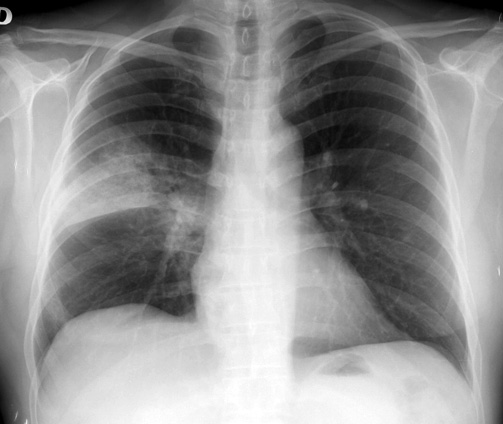

Efectividad de la vacuna antineumocóccica 23-valente en mayores de 65 años

La vacuna redujo en un 33% las neumonías por serotipos incluidos en la vacuna, y en un 27% el total de neumonías por neumococo en esta población. Lancet Infectious Diseases, 23 de enero de 2017